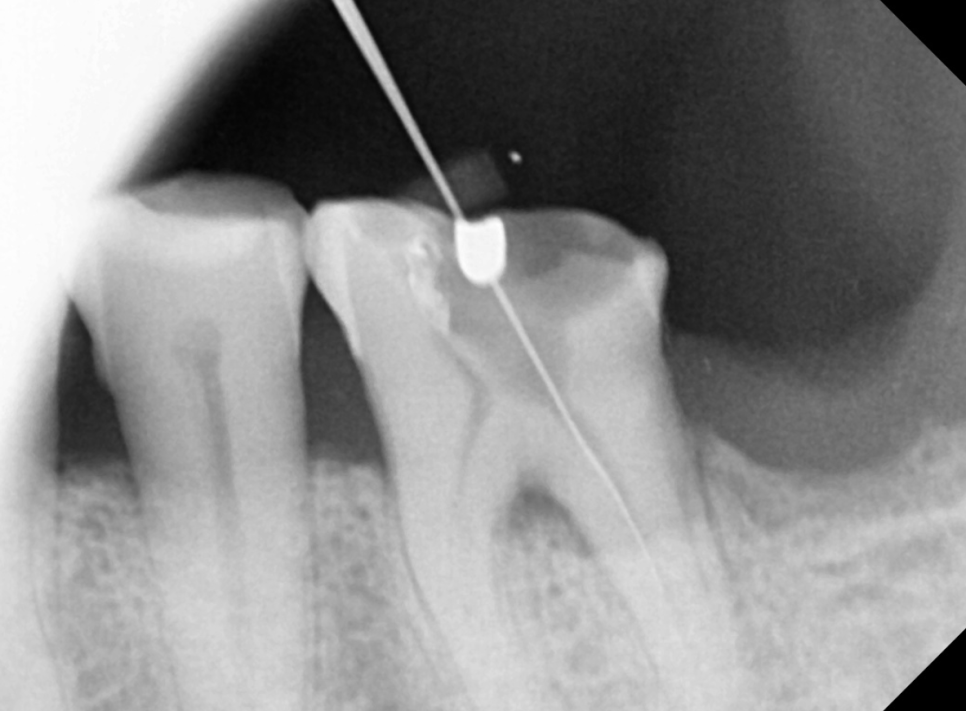

x-ray에서는 뿌러지지 않는 이상 알 수가 없습니다ㅠㅠㅠ

240108

이런 경우 3차원적으로 볼 수 있는 ct를 찍어보는데

치아 뿌리에 금이 관찰됩니다.